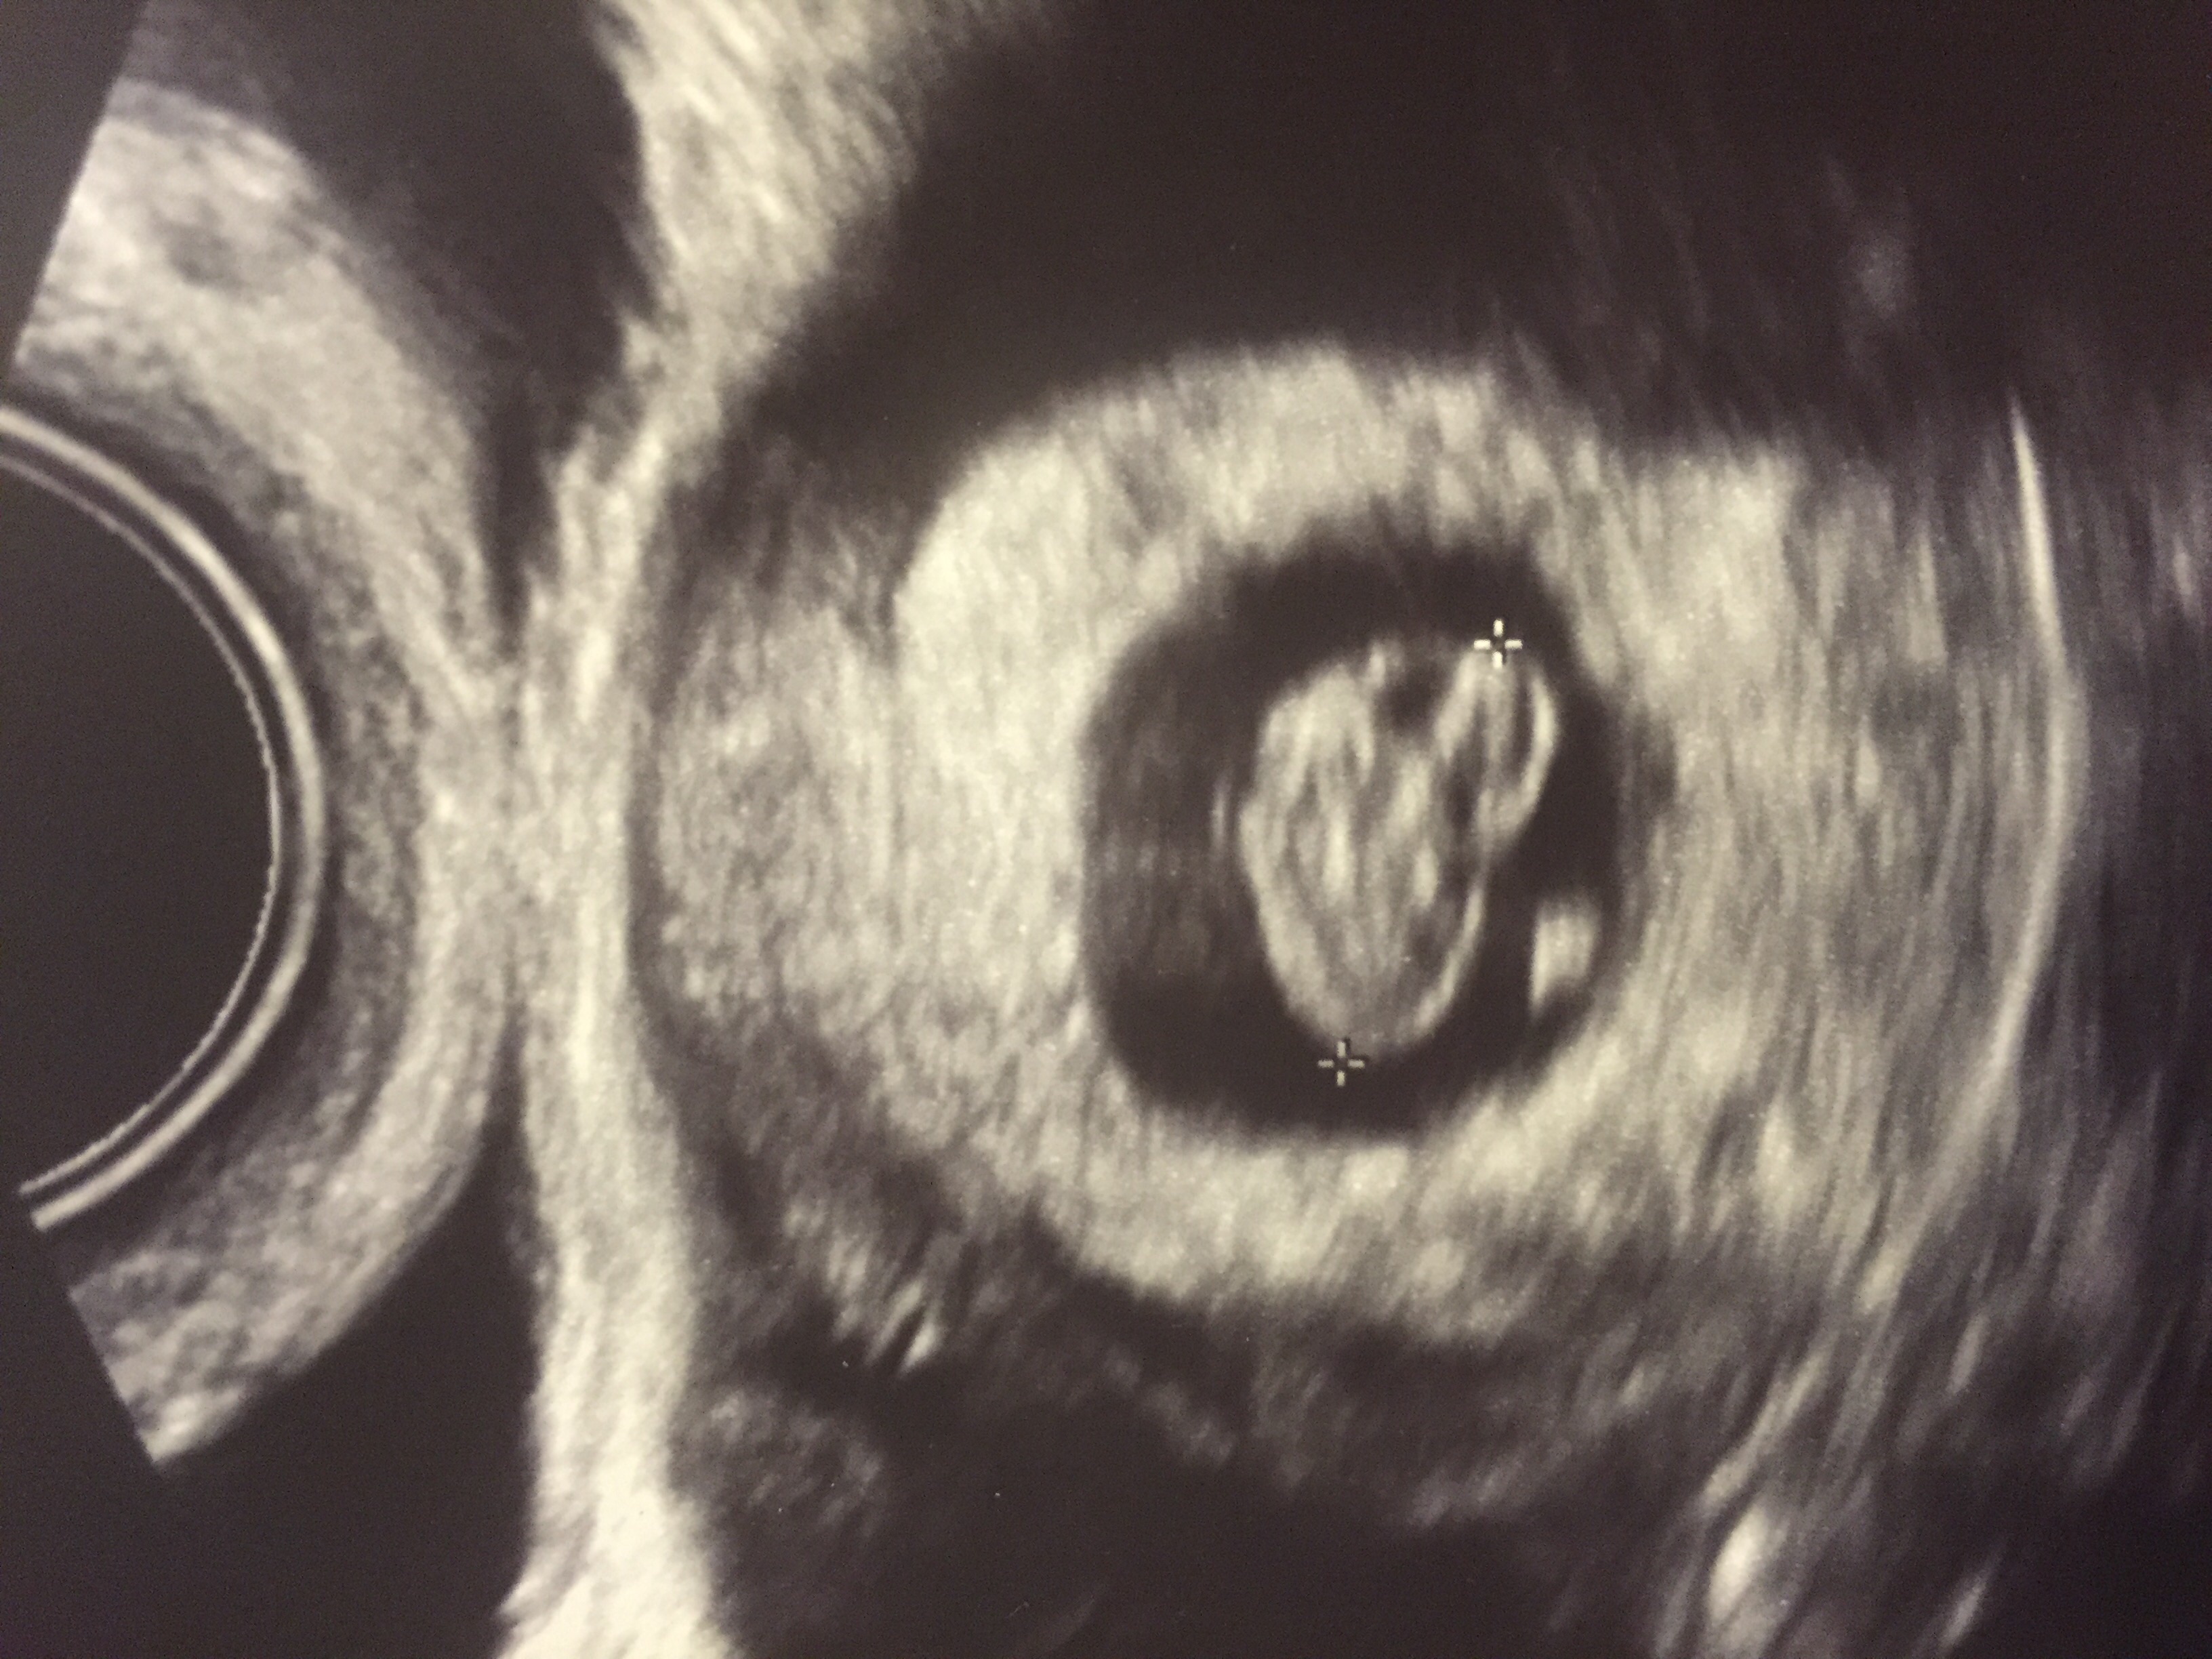

Had my first appointment yesterday and got to meat Bean! (That's what the husband and I call the baby!) We even heard a strong heartbeat!! Today makes 8 weeks!!! Very excited as this is our first!

Size of a Gummy Bear!

I even got to see some movement!!